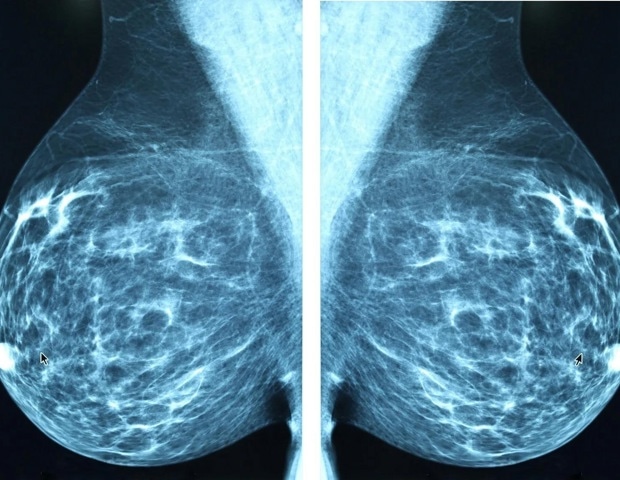

HER2-положительный рак молочной железы составляет примерно 17% всех случаев рака молочной железы и связан с пятилетней выживаемостью менее 50% для пациентов с метастатическим заболеванием. С 2012 года лечение первой линии HER2-положительного метастатического рака молочной железы практически не изменилось и состоит из химиотерапии с последующей поддерживающей терапией двойными моноклональными антителами против HER2, сказала Эрика Гамильтон, доктор медицинских наук, директор исследования рака молочной железы в Научно-исследовательском институте Сары Кэннон (SCRI) в Нэшвилле. В настоящее время у большинства пациентов прогрессирование заболевания наблюдается в течение двух лет после начала лечения, и им часто приходится переходить на химиотерапию.